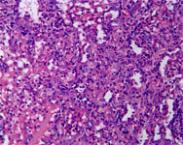

彈性假黃瘤即假性彈性黃色瘤病,又稱皮膚假性黃色瘤(pseudoxanthomaelasticum)、營養不良性彈力纖維病(elastosisdystrophica)、系統性彈力纖維病(systemicelasticdisease)、全身彈力纖維碎裂癥(generalizedelastorrhexis)、遺傳性彈力纖維營養不良癥(hereditaryelastodystrophy)、Gr?nblad-Strandberg綜合征(Gr?nblad-Strandbergsyndrome)、Gr?nblad-Strandberg-Touraine綜合征、Touraine綜合征、Darier-Gr?nblad-Strandberg綜合征等。本病征是一種罕見的全身結締組織病,呈廣泛的彈性組織變性。本綜合征具有4個特征:皮膚假性彈性黃色瘤;視網膜血管樣條紋;復發性嚴重的消化道出血;脈搏減弱。